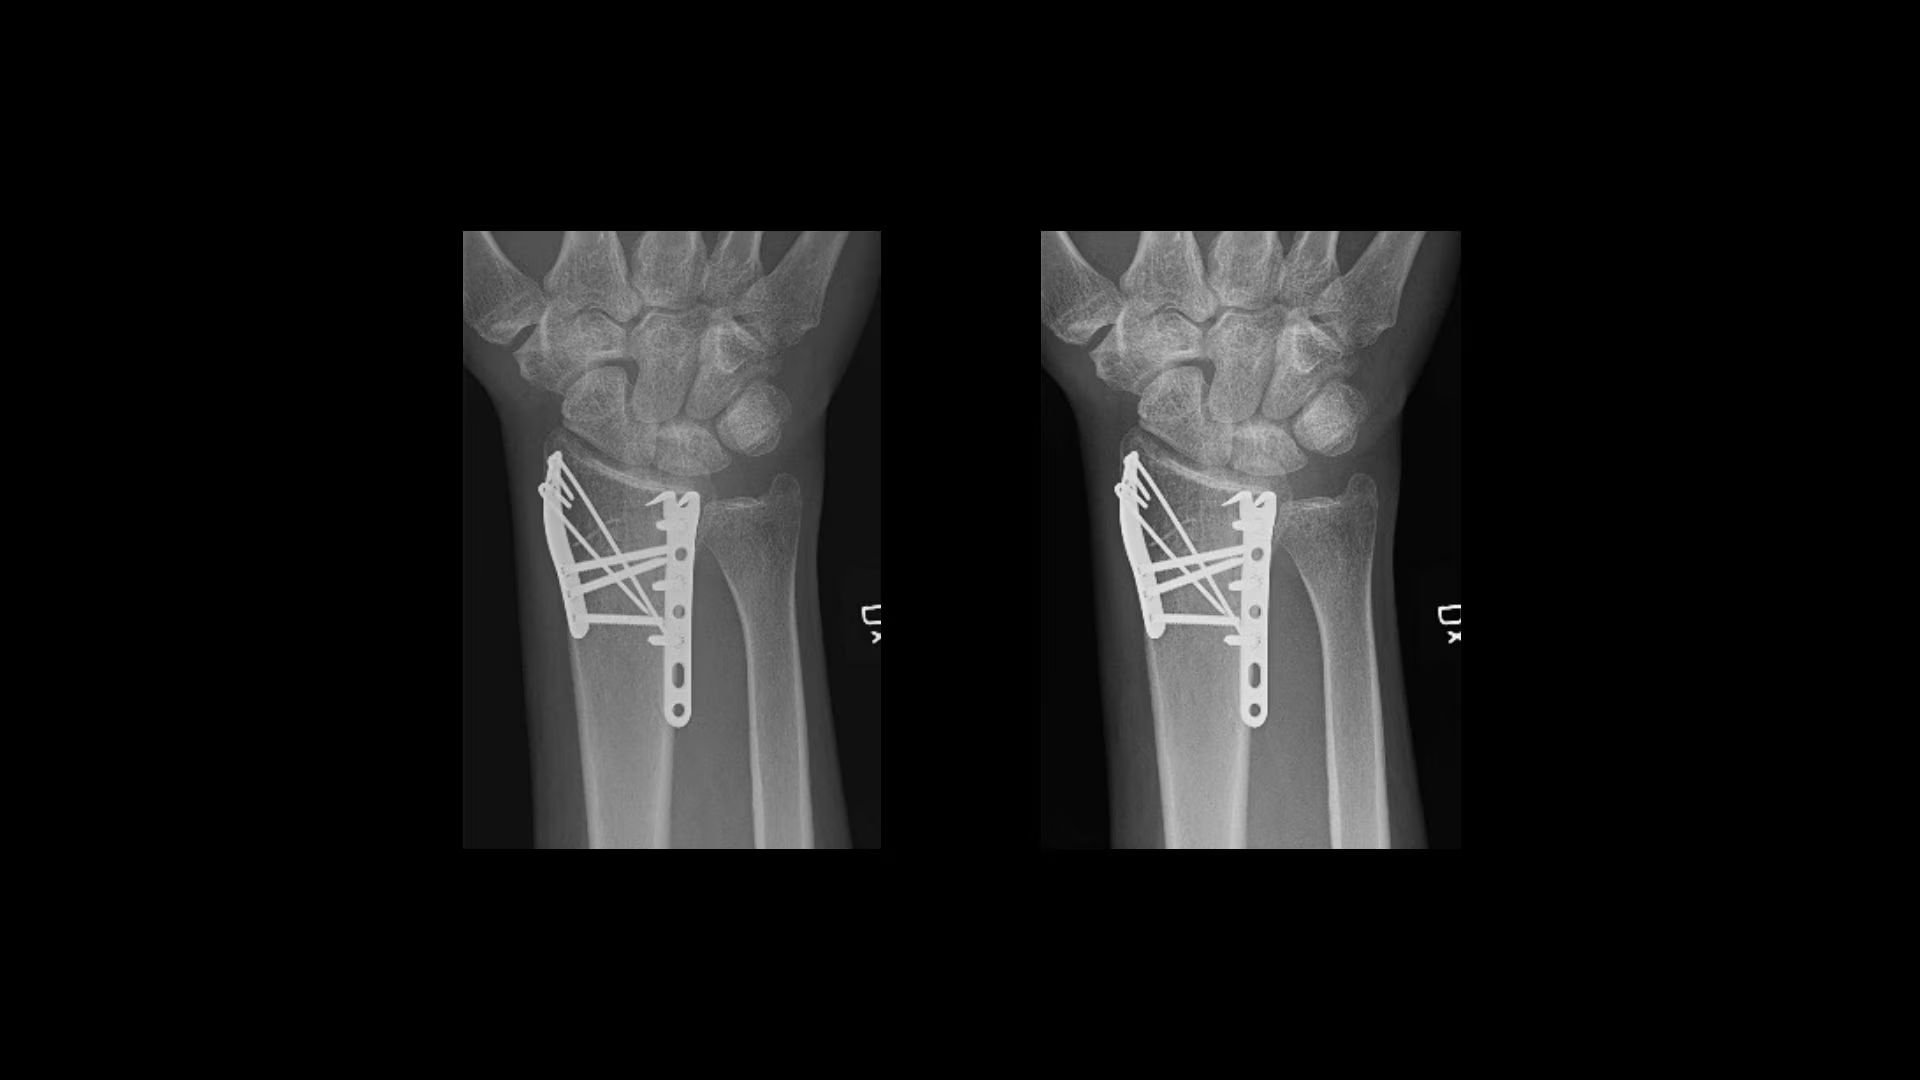

Flexibility

Reach a diagnosis, quickly

Helix offers four predefined sets of anatomy- and view-specific “looks” for different levels of contrast, brightness, edge enhancement, noise reduction and tissue equalization.

Real-time IP Looks provides faster and easier fine-tuned customizations.

IQ Compare allows for simultaneous viewing of standard and customized looks to simplify comparisons.

QuickEnhance offers one-touch reprocessing of images with a custom look. It is customizable by anatomy for multiple uses, including instrument check, implant visualisation and line placement.